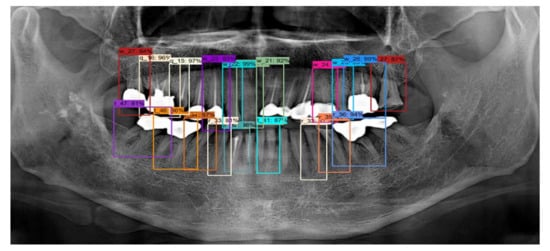

By contrast, for the case of implant fixtures and crowns, the accuracies were 45.1% and 50.9%, respectively, as shown in Table 2 when IOU = 0.5. Further, at IOU = 0.7, low accuracies of 26.6% and 40.8% were obtained for implant fixtures and crowns, respectively. These results indicate that the shapes of the implant fixtures and crowns are detected less accurately than expected. One possible reason for this is that the crowns and implant fixtures have various unstructured shapes, and hence the model may be unable to accurately detect the shapes when compared to normal teeth. Nevertheless, the results obtained are significant because the implant fixtures and crowns were still detected through the panoramic images. Therefore, as shown in Figure 9, each tooth, implant, and crown can be detected. As described above, the numbering of the teeth, the implant, and the crown is determined by detecting the teeth.

Figure 9. (a) Example of tooth, (b) crown, and (c) implant fixture detection.